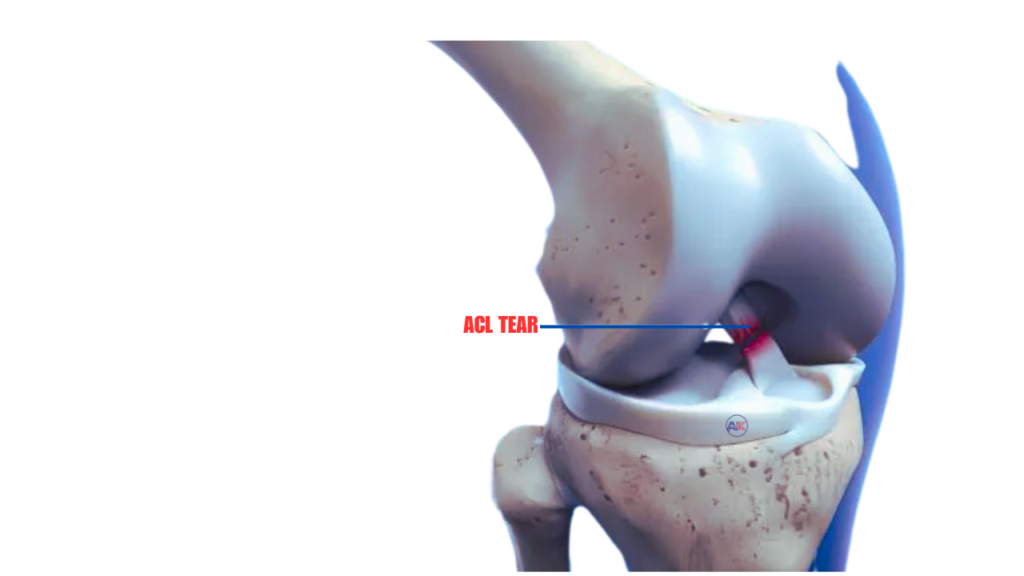

ACL TEAR, RUPTURE, INSTABILITY, OR INJURY

Injuries to the anterior cruciate ligament (ACL) in the knee can lead to tears, ruptures, or instability, often causing pain and affecting knee function.